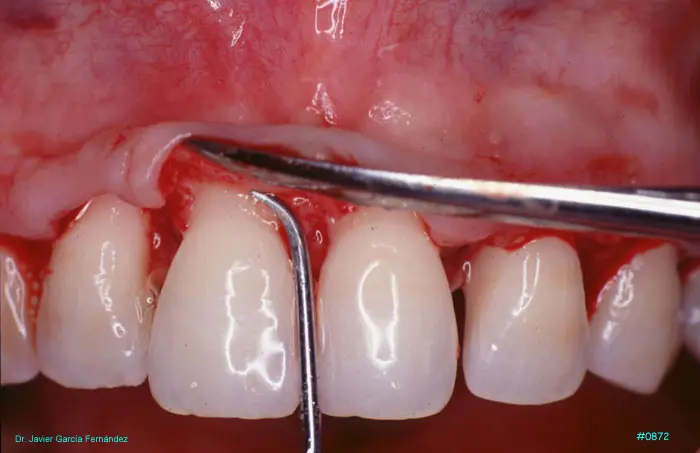

Atlas of Surgical Techniques in Periodontics. Chapter III. Atlas de Técnicas Quirúrgicas en Periodoncia